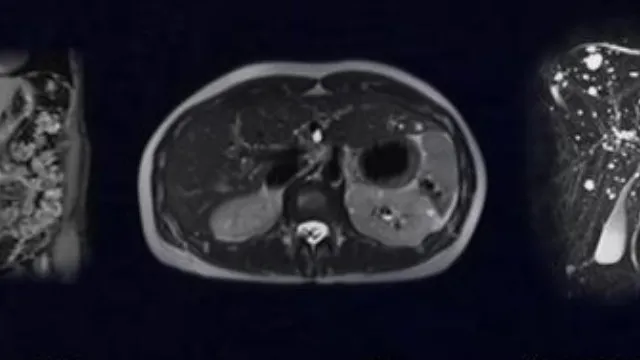

Une édition sur le thème de "l'IRM abdominale à ingérer et digérer" avec au programme exposés, présentation de cas et échanges d'expériences. A cette occasion, plusieurs collaborateurs et collaboratrices des HUG prendront la parole :